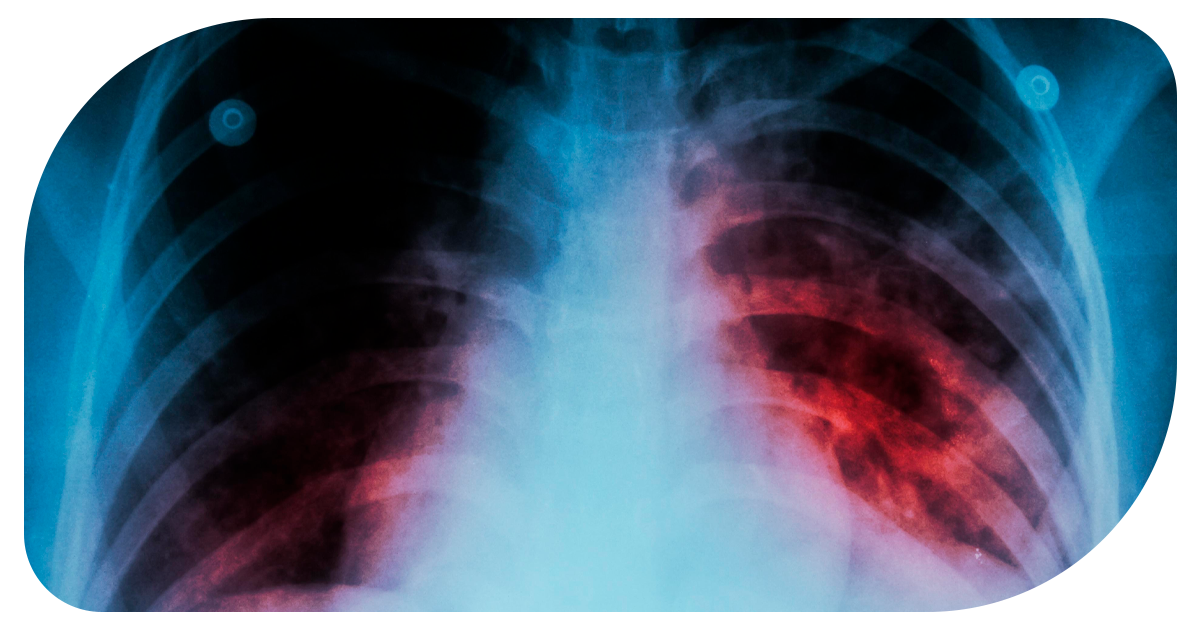

Ejemplo de Imagen informativa 2